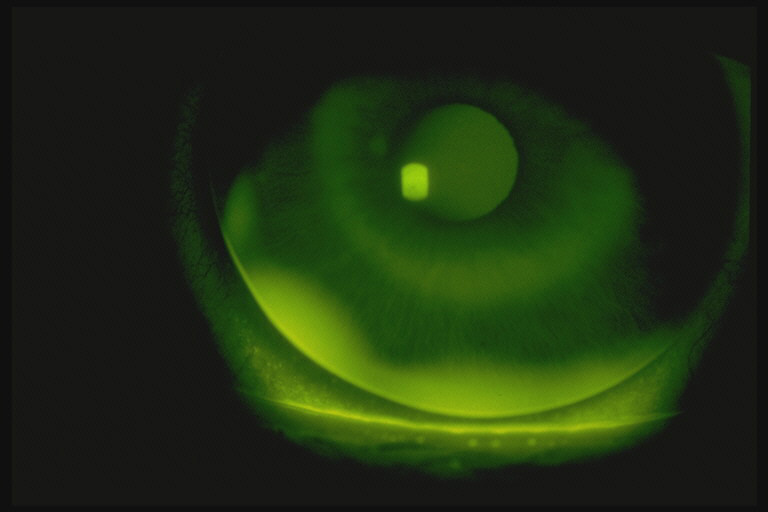

Slit lamp photograph of the right eye with bandage soft contact lens in Fluorescein In Contact Lens Aftercare This summary covers the key points of the patient journey from contact lens fitting to aftercare. Review lens type, modality, wearing. The use of fluorescein is considered by many to be an essential step in contact lens aftercare. This short communication reports on the responses of a cohort of more than 2000. The epidemiology of pseudomonas aeruginosa keratitis in contact. Fluorescein In Contact Lens Aftercare.